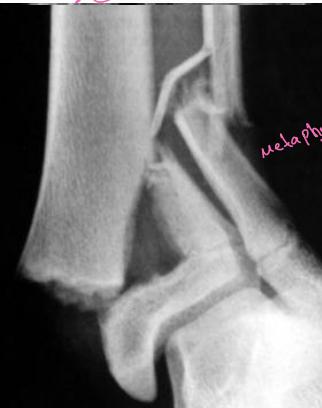

Classification – Salter-Harris

- Type I - Through the physis

- Type II - Through the physis with small piece of metaphysis (75%)

- Type III - Through the physis and extend to intra-articular

- Type IV - Metaphysis + physis + Intra-articular

- Type V - Cause growth arrest “Compression”